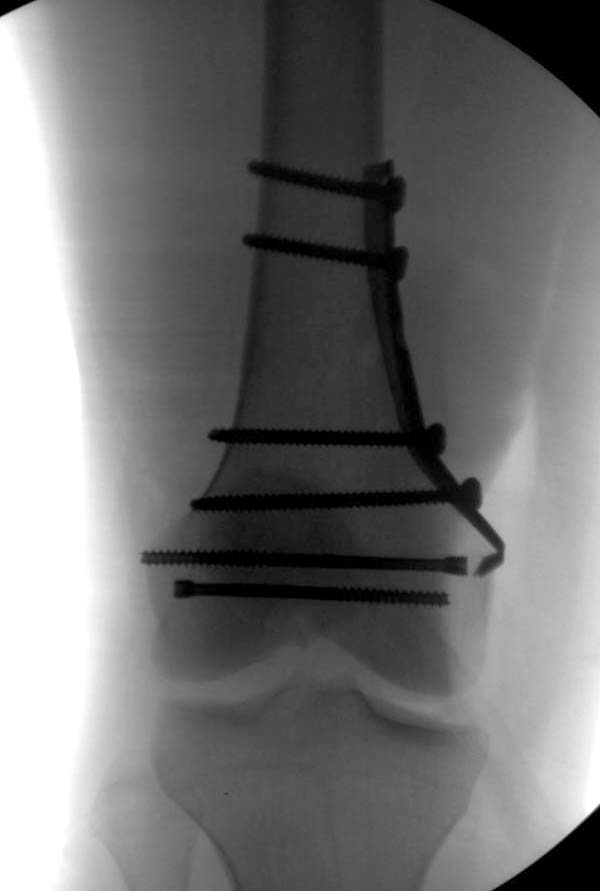

[Ortho] Нелеченный перелом Hoffa

Здесь представлены различные варианты фиксации перелома, а также снимки

комбинации перелома с повреждением хряща (12-19). Пластика хряща

OsseoFit и установка custom made plate.